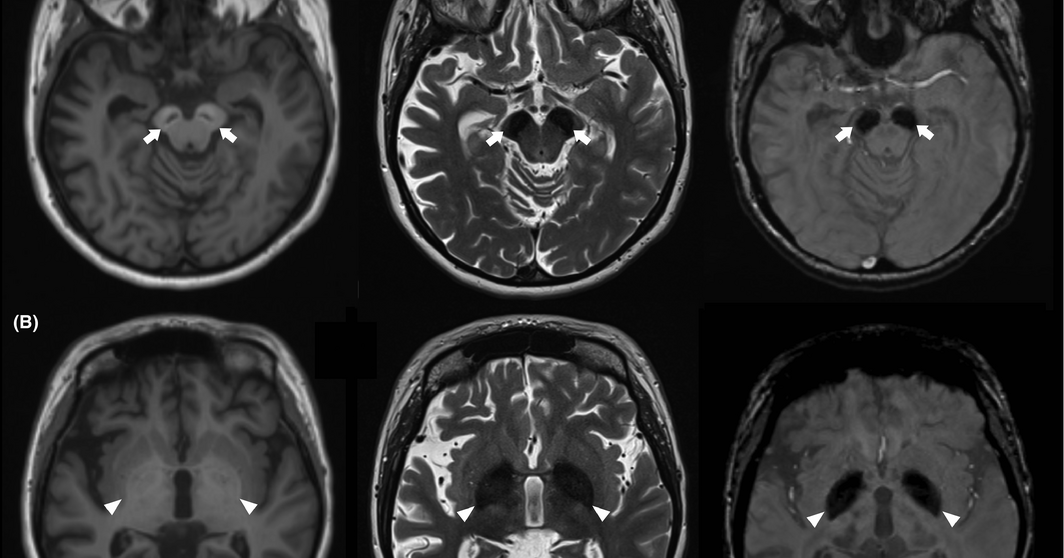

MRI and DAT scan findings of betapropeller proteinassociated... Download Scientific Diagram Propeller Beta Beta range, in a turboprop engine, is the range of power lever positions between flight idle and maximum reverse. Putting the propeller into reverse mode (beta mode) and maintaining rpm control in reverse is accomplished through the use of the. Alpha is the mode for all flight operations including takeoff. 39 rows the propeller has 2 modes, alpha and beta.. Propeller Beta.

(PDF) Neuropathology of Betapropeller protein associated neurodegeneration (BPAN) a new tauopathy